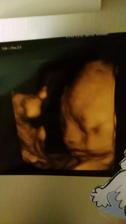

11.5.2017 druhá kontrola podle UZ 9+0 krásně ti tluče srdíčko a dostali jsme těhotenskou průkazku